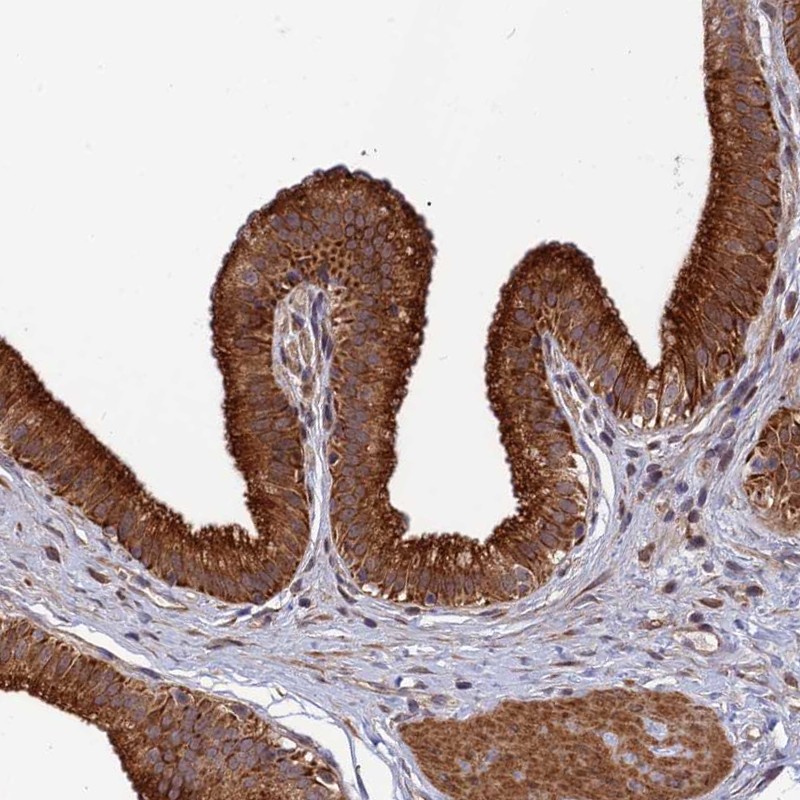

Immunohistochemical staining of human gallbladder shows cytoplasmic positivity in glandular cells.